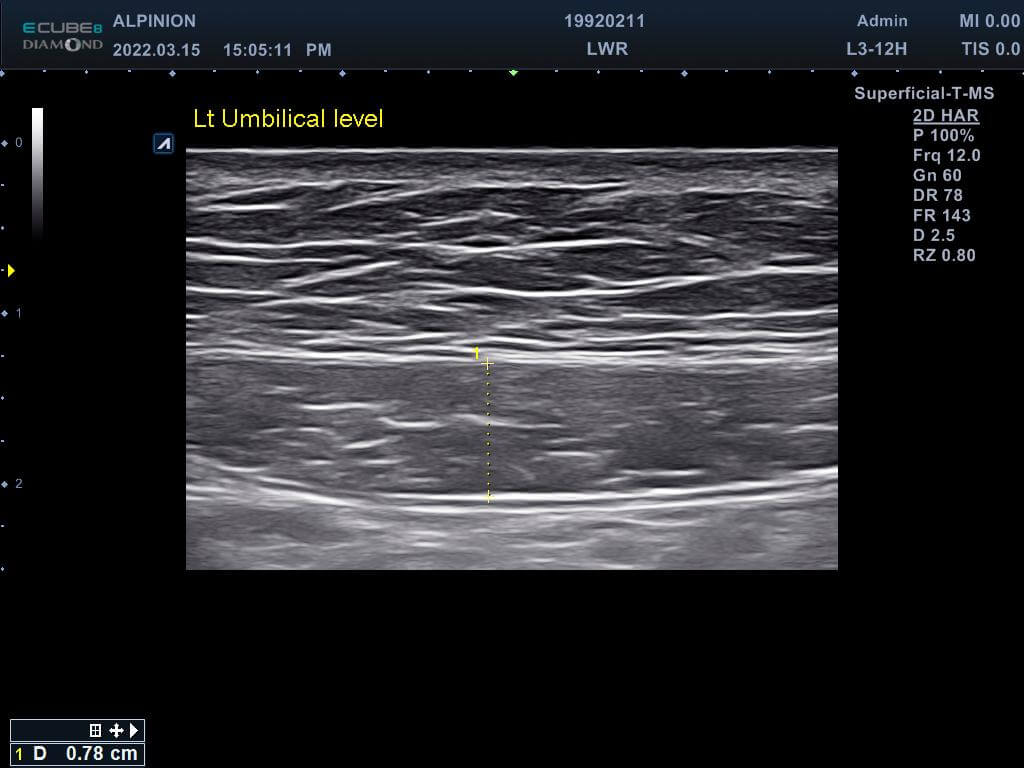

專業的醫師先在磁刺激前測量林小姐的腹直肌厚度,發現雙側的腹直肌分別為0.81cm(右側)與0.78cm(左側),同時雙側白線的距離也長達1.96cm,已經達到腹直肌分離的狀況。在使用了四周共8次的增肌減脂機後,雙側的腹直肌增厚為0.93cm(右側)與0.82cm(左側),同時雙側白線的距離減少1.46cm並明顯增厚,代表結締組織已經增生修復了。

增肌減脂(前)左側肚臍高度腹直肌0.78cm